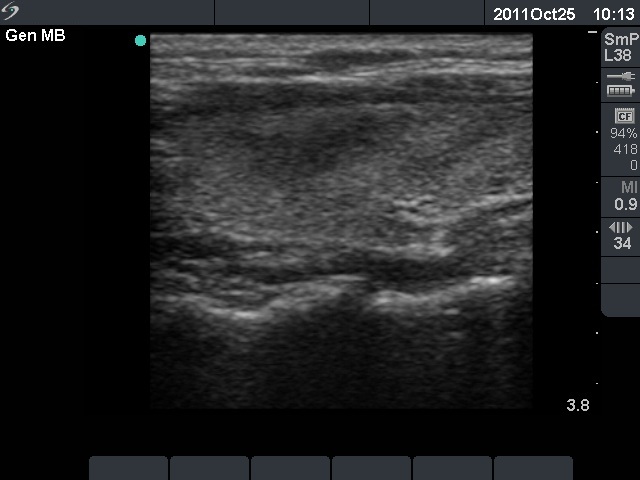

50 months after init. investig. |

0 |

43 months after delivery |

Nothing |

- |

1.55 |

17.2 |